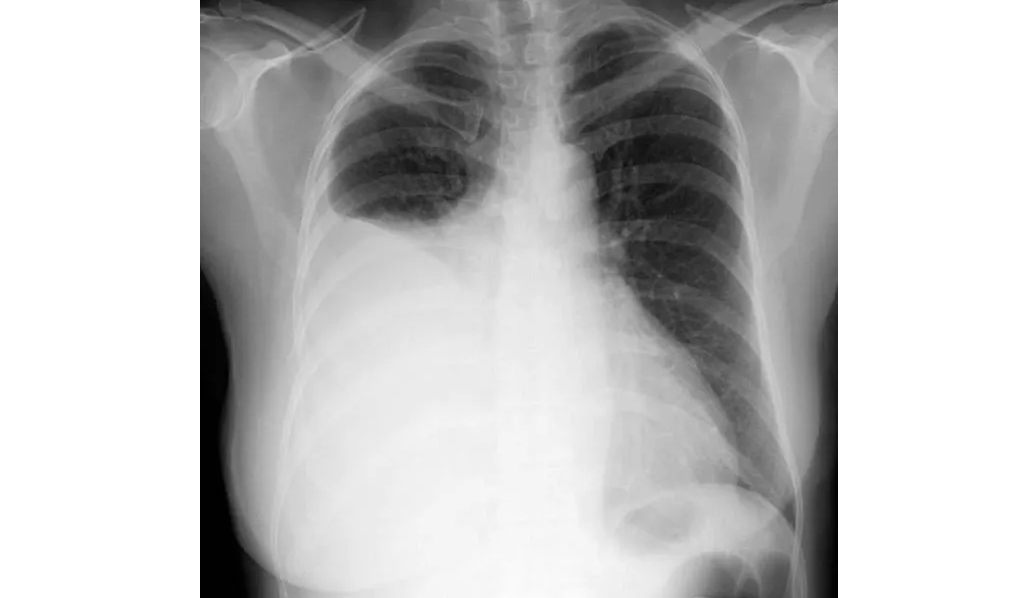

Farmacocinética de los antibióticos en derrames pleurales infectados.

En este estudio sobre farmacocinética de antibióticos realizado en pacientes con derrames pleurales infectados se encontró que los antibióticos de uso común, como amoxicilina, metronidazol, piperacilina-tazobactam y clindamicina, alcanzan niveles en el líquido pleural equivalentes a los de la sangre y por encima de la CIM para las bacterias que se sabe que causan infección pleural. La preocupación sobre la penetración de antibióticos de uso común en el espacio pleural infectado (excepto por la trimetroprima) son infundadas. Thorax, 4 de julio de 2024.